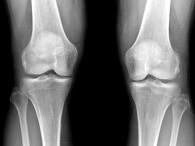

问题 女,65岁,右膝痛,活动受限,结合图像,最可能的诊断是?(?)

选项 A.神经性关节病 B.创伤性关节炎 C.退行性骨关节病 D.类风湿关节炎 E.痛风

答案 C